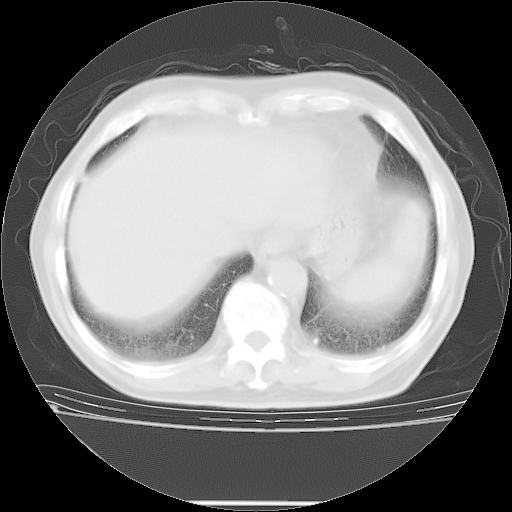

今天复查肺部CT,发现双肺广泛磨玻璃样改变。所以我把3月19日和5月9日相隔50天的肺部CT上传。请大家会诊。

2009年3月19日肺部CT片。

2009年3月19日肺部CT

5月9日肺部CT(在4月27日齐鲁医院肺部CT描述部分肺组织磨玻璃样改变,12天后肺组织广泛磨玻璃样改变)

大致读了系列胸部CT:纵隔窗无明显异常,肺窗:从4、27至今:主要是双肺中下野外带可见毛玻璃样改变,目前处于急性肺泡炎阶段,至于原因考虑1、结替组织或胶原血管性疾病所致?2、恶性疾病如恶组在肺部所致的表现或细支气管肺泡癌?3、药物或其它原因如肺蛋白沉着症所致肺泡炎目前不太可能?总之,明天就去请我院的呼吸科、感染科、血液科和临免专家会诊哈。